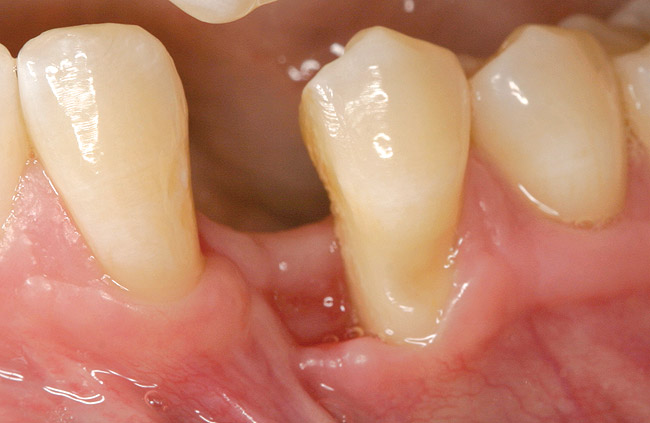

Figure 4  Vertical ridge defect in site No. 22.

Figure 4

Figure 6  Mucogingival and residual defect after removal of implant in site No. 22.

Figure 6